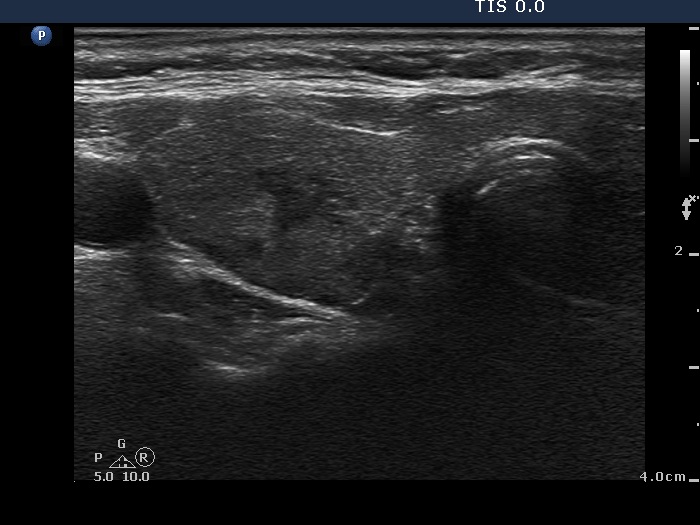

First examination (first and second rows of images):

Ultrasonography. A diffusely hypoechogenic thyroid was found with multiple lesions. There was a hypoechogenic lesion in the dorsal part of the right lobe. This lesion showed taller-than-wide and longer-than-wide shape. The left lobe had two lesions which were more echogenic than the non-nodular part of the lobe, however less echogenic than a normal, healthy thyroid.